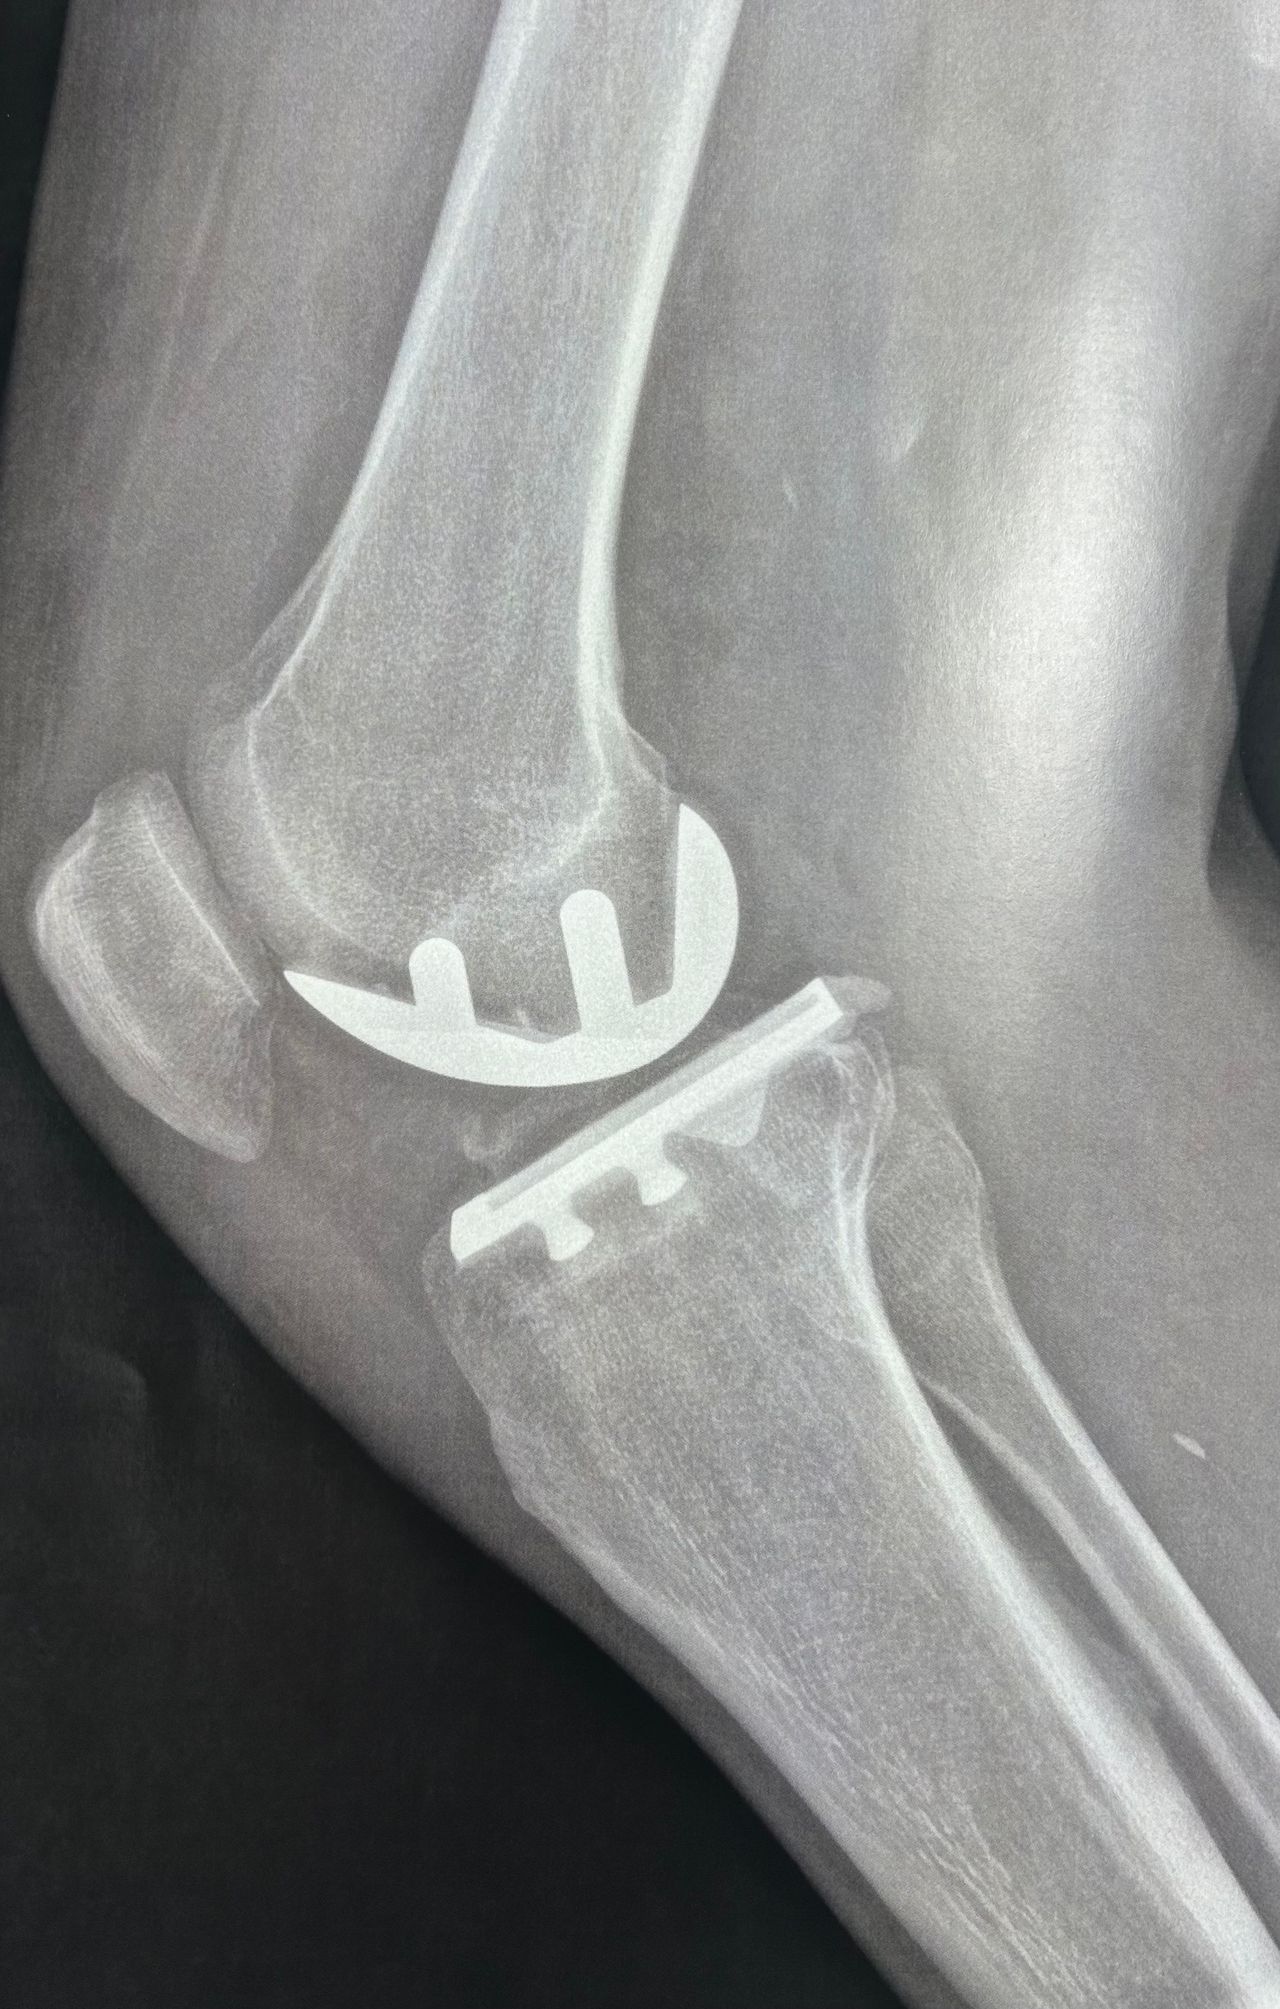

Foto e video

Per una maggiore completezza della visita è utile avere a dispozione almeno una Radiografia standard o Risonanza Magnetica recenti.